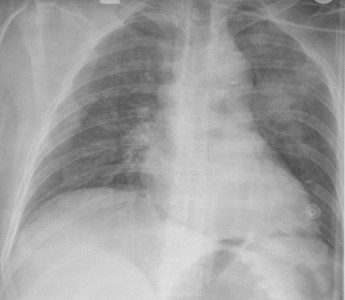

SIGNO DE LA PLEURA VISIBLE

Las flechas señalan la pleura despegada del mediastino.

La presencia de neumomediastino provoca el despegamiento lateral de las dos hojas pleurales. En la radiografía PA de tórax esta imagen es más fácilmente visible en el margen izquierdo de la silueta cardiomediastínica. La pleura despegada es visible como una línea radioopaca que tiene un recorrido más o menos paralelo al contorno cardiomediastínico.